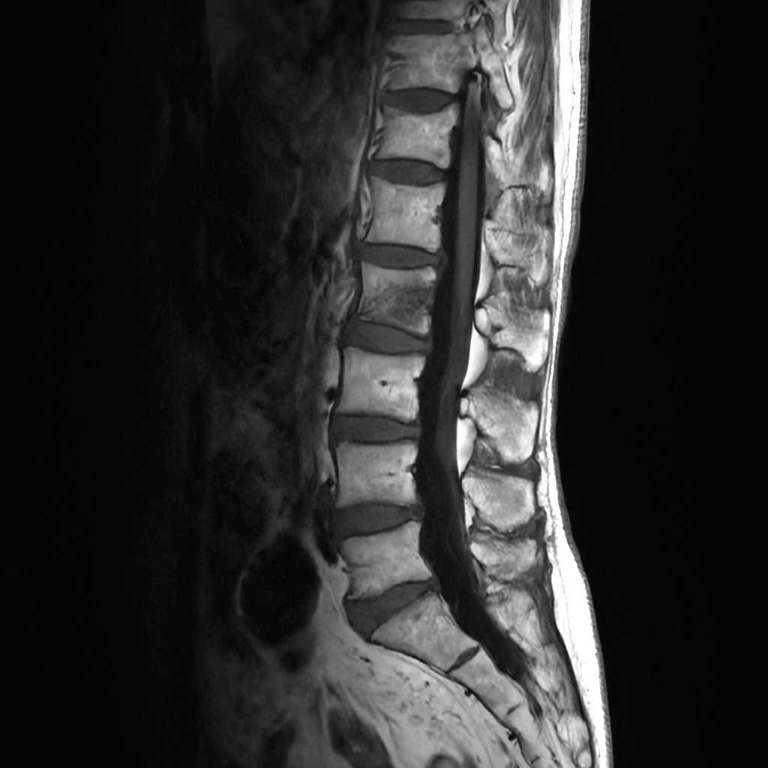

整形外科領域

脊椎

椎間板ヘルニア